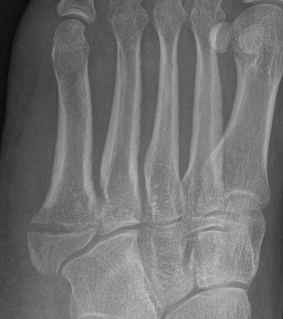

Displaced fracture Nonunion

Screw fixation Zone 2 nonunion

Screw fixation Zone 3 nonunion